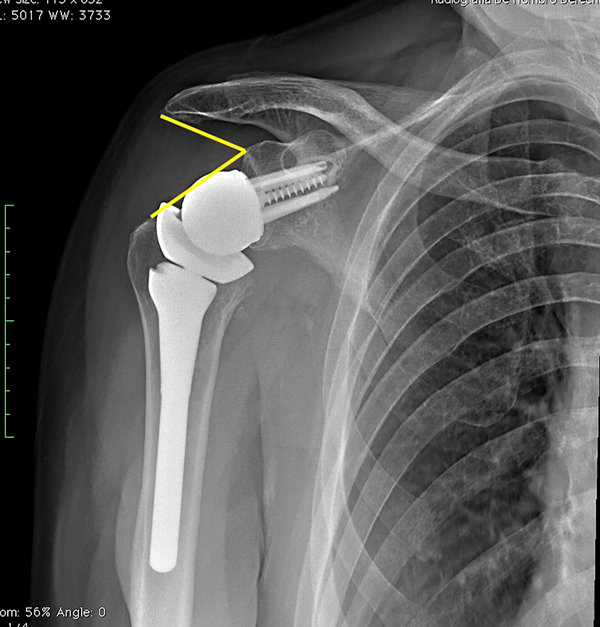

En todos los pacientes se realizó una radiografía postoperatoria con una proyección lateral y AP verdadera de hombro para evaluar las mediciones radiográficas de acuerdo a lo descripto por Boutsadis.6 El LSA fue medido desde el punto más superior y lateral del tubérculo glenoideo, el punto más lateral del acromion y el borde más lateral de la tuberosidad mayor (fig. 1). El DSA fue tomado desde el punto más lateral del acromion el tubérculo glenoideo y el borde más superior de la tuberosidad mayor (fig. 2). Para evaluar la reproducibilidad de las mediciones, estas fueron tomadas por tres de los autores (un médico general, un cirujano de hombro, un fellow en cirugía de hombro) y se evaluó la concordancia entre ellos.

Figura 2: Medición de ángulo de distalización.